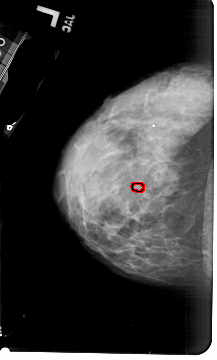

A_1797_1.LEFT_CC

LEFT_CC LINES 5386 PIXELS_PER_LINE 3241 BITS_PER_PIXEL 12 RESOLUTION 43.5 OVERLAY

FILE: A_1797_1.LEFT_CC.OVERLAY

TOTAL_ABNORMALITIES 1

ABNORMALITY 1

LESION_TYPE CALCIFICATION TYPE PUNCTATE DISTRIBUTION CLUSTERED

ASSESSMENT 4

SUBTLETY 2

PATHOLOGY BENIGN

TOTAL_OUTLINES 1